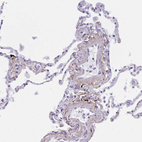

Immunohistochemical staining of human lung shows moderate positivity in the extracellular matrix in blood vessels.